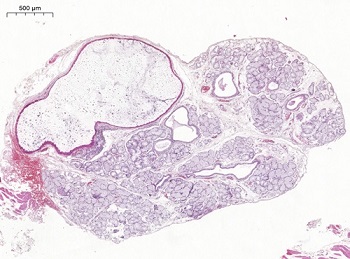

For confirmation, an excisional biopsy of the initially referred nodule was performed under local anesthesia with mepivacaine hydrochloride 2% (20 mg/mL) + epinephrine 1:100.000 (μg/mL), and the specimen was sent to the oral and maxillofacial pathology laboratory. Microscopic examination of histological sections revealed cystic lesions lined by cuboidal, columnar, or squamous epithelium with two to three cellular layers, sometimes displaying ciliated cells, with áreas of apocrine and mucous metaplasia. The lumen contained mucous material mixed with some inflammatory and desquamated epithelial cells. The lesions were associated with lobules of MSGs exhibiting multiple significantly dilated ducts (Figures 6, 7, and 8). Based on the clinicopathological correlation features, the final diagnosis of MISDC was established.

Figure 6. Histopathological aspects of the multiple cystic lesions associated with lobules of MSGs (hematoxylin and eosin stain, 2X original magnification).

Figure 7. MSG showing a cystically dilated interlobular duct and significantly dilated intralobular ducts. A variable amount of mucus is present in the lumen (hematoxylin and eosin stain, 5X original magnification).

Figure 8. Cystic lining epithelium with a gradual transition in thickness, showing, in the thicker portion, epithelial cells with apocrine metaplasia, pseudostratified columnar cells with mucus and cilia, and cells with mucous metaplasia; and in the thinner portion, columnar, cuboidal, and squamous cells (hematoxylin and eosin stain, 20X original magnification).

Given the clinical similarities among these differential diagnoses, analysis of histopathological characteristics is essential for distinguishing among the entities. As in the present case, all reported cases of MISDC revealed cystically dilated ducts lined by cuboidal, squamous, and/or pseudostratified columnar epithelium containing mucus, in addition to a lumen filled with mucous material (Table 2). In contrast, a mucocele presents as a cavity lined by granulation tissue, rather than epithelial tissue, a key histological difference that distinguishes it from MISDC.1, 2, 16 In turn, canalicular adenoma is characterized by the proliferation of narrow and elongated ductal structures that connect in networks,13, 14 a pattern absent in MISDC. On the other hand, cystadenomas of the salivary glands may show similar dilated ducts but differ from MISDC by the absence of a capsule and the presence of an adenomatous component and papillary projections with a fibrovascular nucleus.1, 15